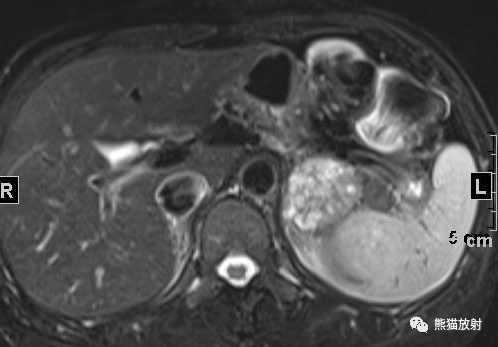

女性,47岁,阵发性头晕、视物模糊4年余,查体发现肾上腺占位。

行肾上腺MRI平扫+增强扫描

⭐️ 左侧肾上腺皮质腺瘤,合并髓样脂肪瘤

? 病灶内含成熟脂肪和脂质成份,在T1反相位和压脂像上局部信号减低。